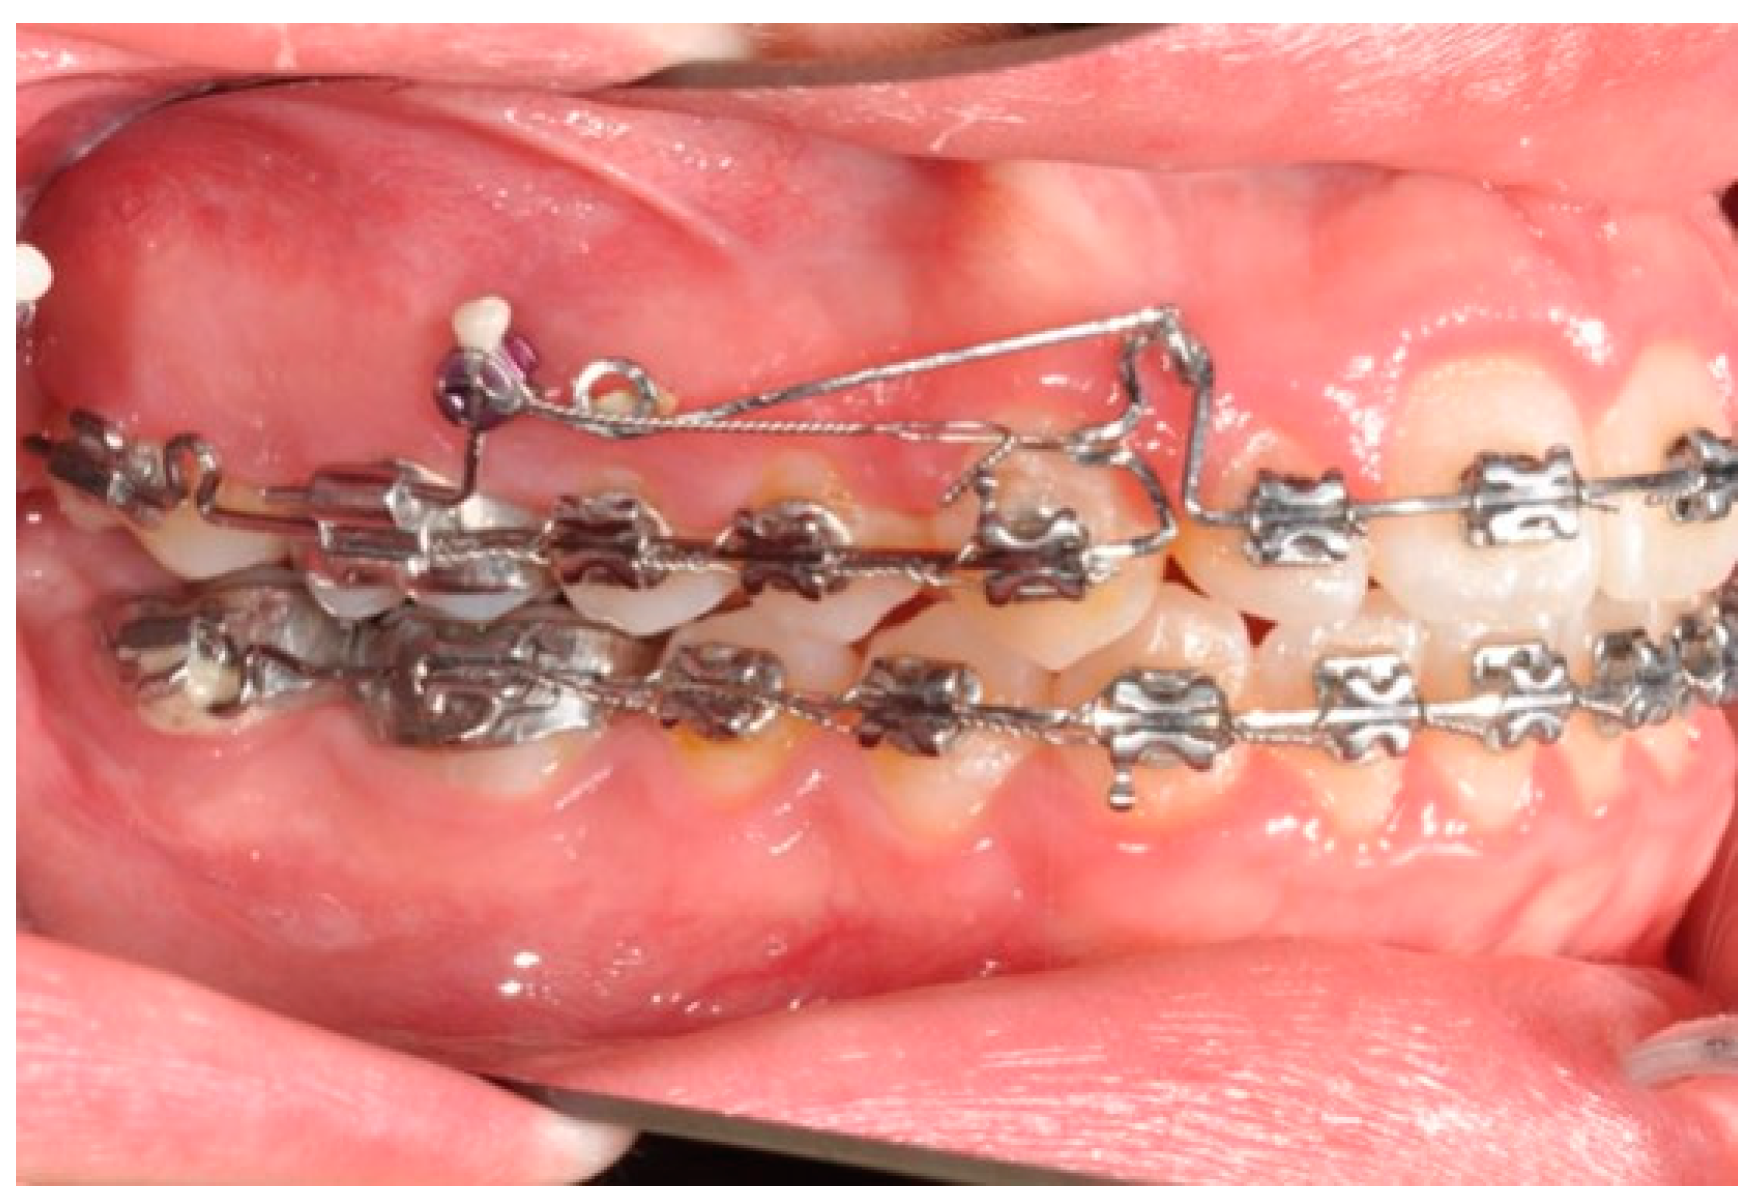

2.2. Molars’ and Premolars’ Distalization